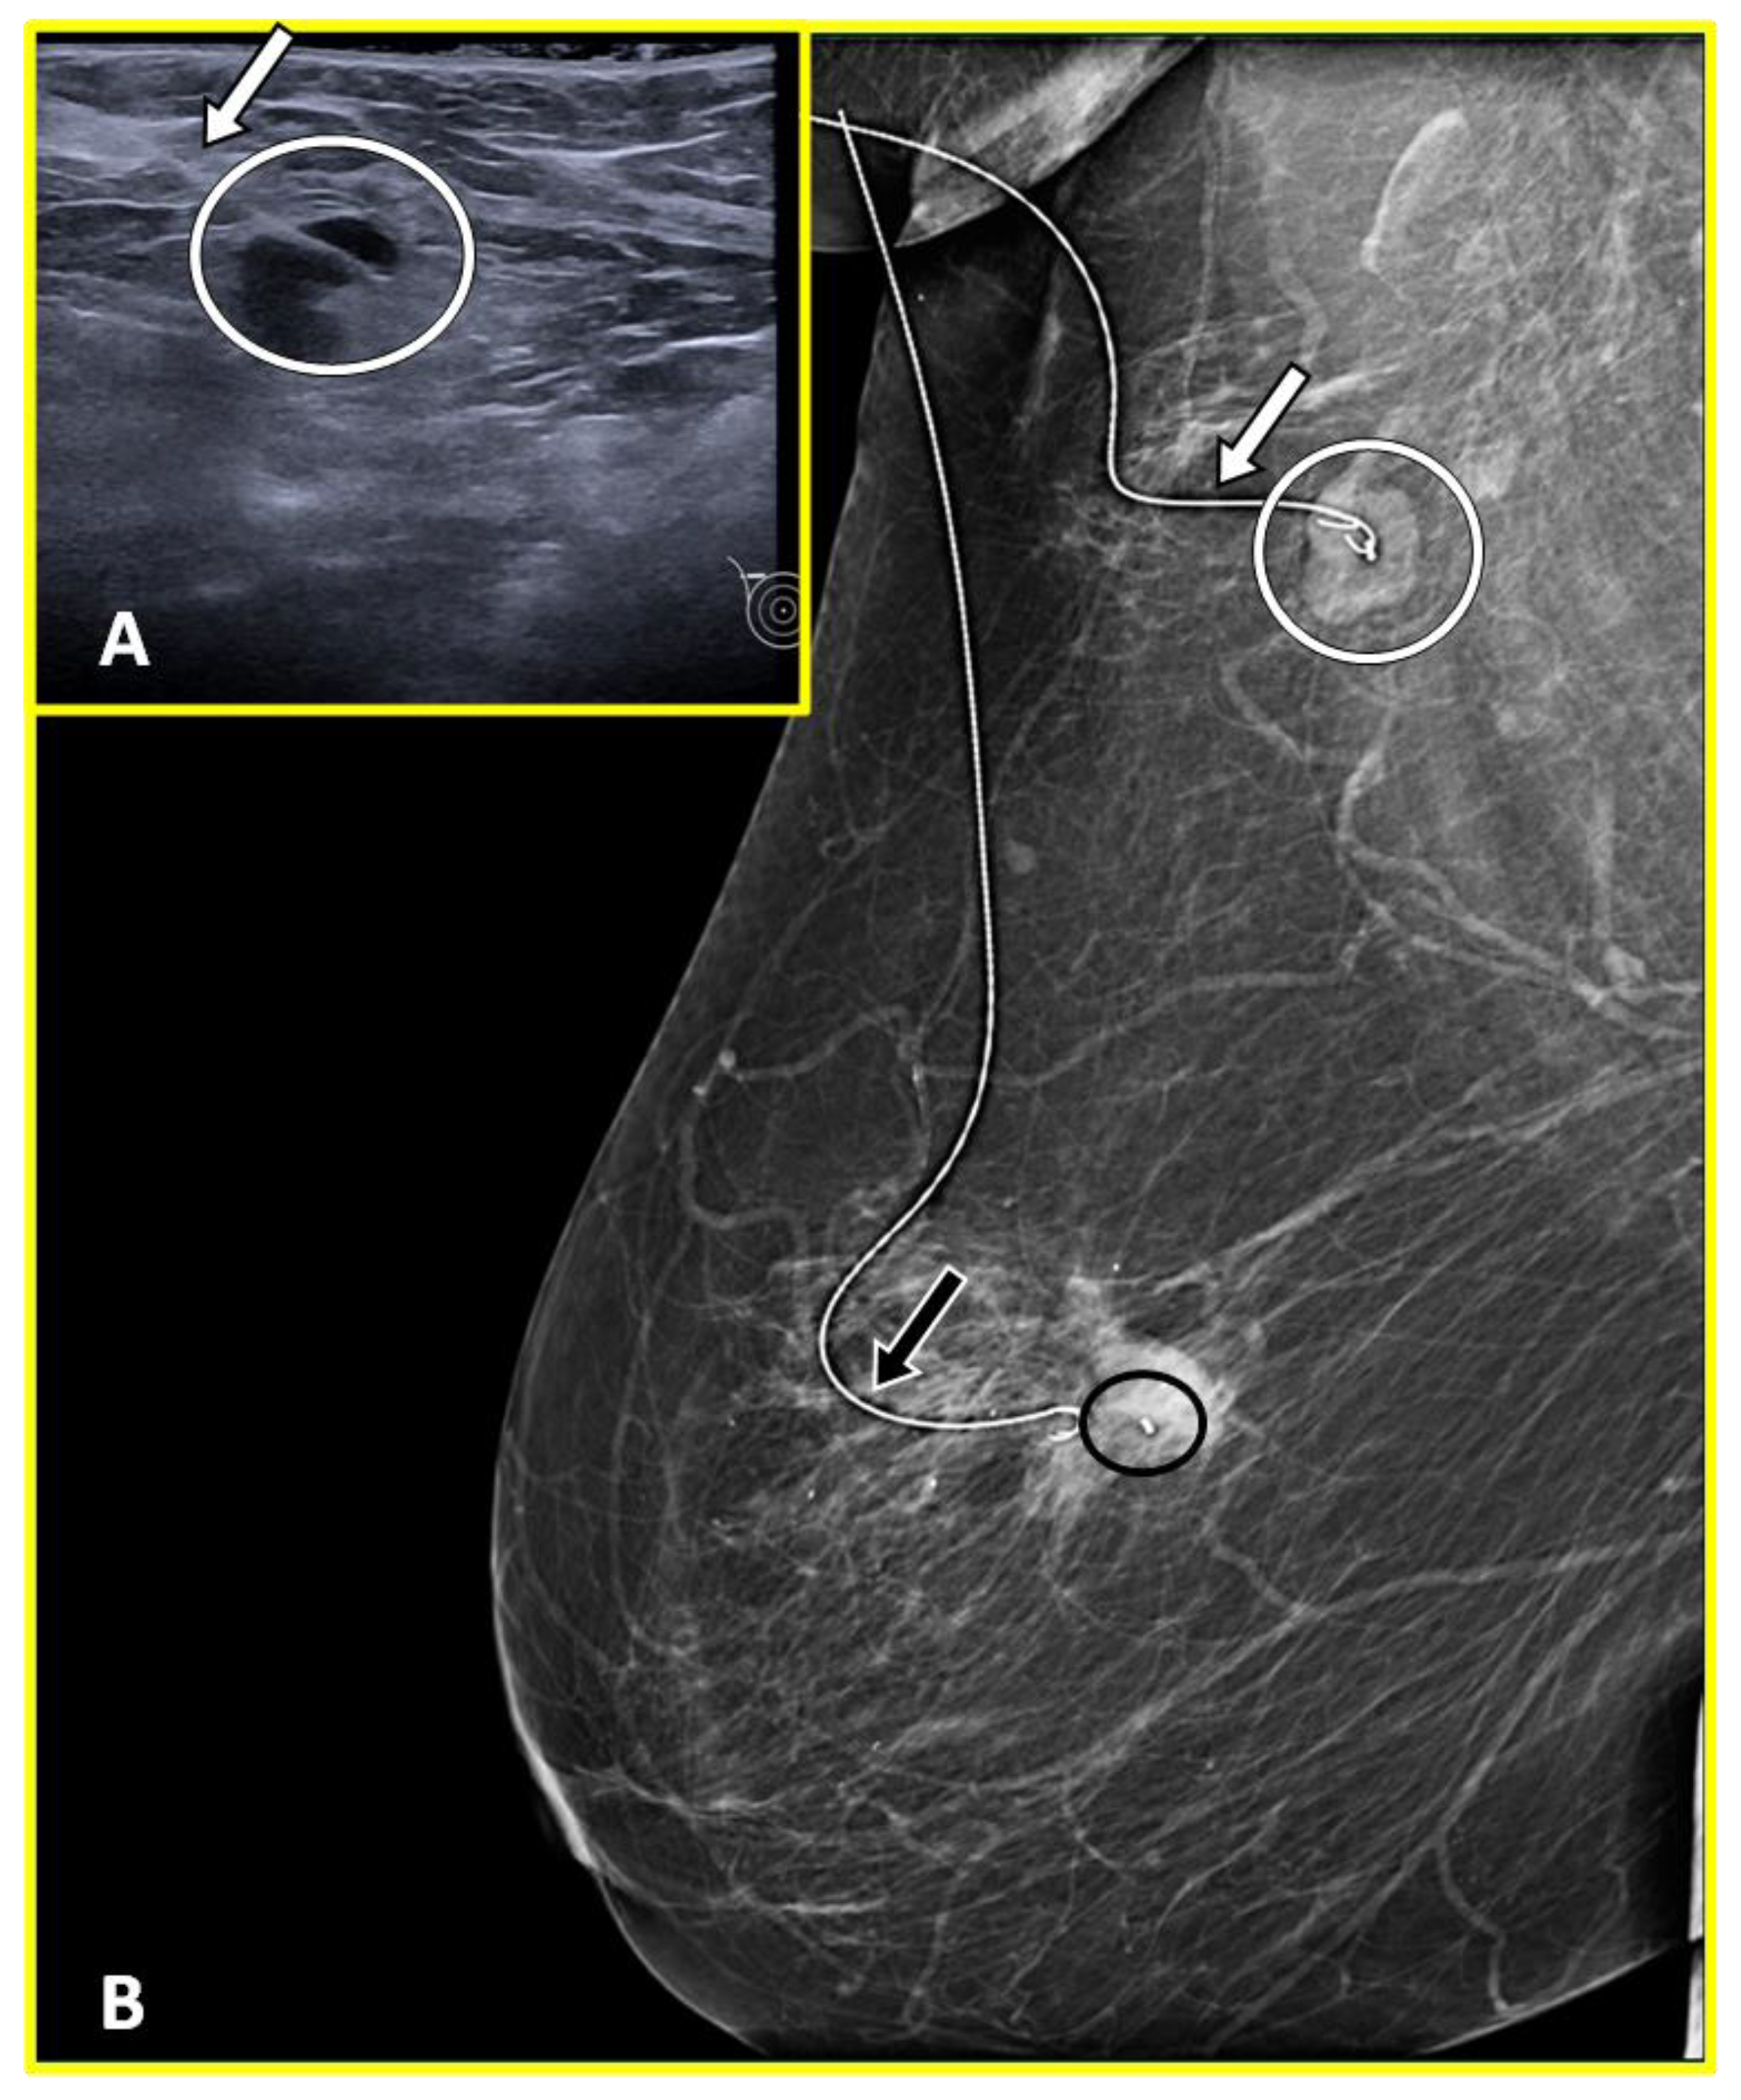

2.1. Marker Clips and Intraoperative Ultrasonography

- Siso, C.; de Torres, J.; Esgueva-Colmenarejo, A.; Espinosa-Bravo, M.; Rus, N.; Cordoba, O.; Rodriguez, R.; Peg, V.; Rubio, I.T. Intraoperative Ultrasound-Guided Excision of Axillary Clip in Patients with Node-Positive Breast Cancer Treated with Neoadjuvant Therapy (ILINA Trial): A New Tool to Guide the Excision of the Clipped Node After Neoadjuvant Treatment. Ann. Surg. Oncol. 2018, 25, 784–791. [Google Scholar] [CrossRef]

- Boughey, J.C.; Ballman, K.V.; Le-Petross, H.T.; McCall, L.M.; Mittendorf, E.A.; Ahrendt, G.M.; Wilke, L.G.; Taback, B.; Feliberti, E.C.; Hunt, K.K. Identification and Resection of Clipped Node Decreases the False-Negative Rate of Sentinel Lymph Node Surgery in Patients Presenting With Node-Positive Breast Cancer (T0-T4, N1-N2) Who Receive Neoadjuvant Chemotherapy: Results From ACOSOG Z1071 (Alliance). Ann. Surg. 2016, 263, 802–807. [Google Scholar] [CrossRef] [PubMed]

- Caudle, A.S.; Yang, W.T.; Krishnamurthy, S.; Mittendorf, E.A.; Black, D.M.; Gilcrease, M.Z.; Bedrosian, I.; Hobbs, B.P.; DeSnyder, S.M.; Hwang, R.F.; et al. Improved Axillary Evaluation Following Neoadjuvant Therapy for Patients With Node-Positive Breast Cancer Using Selective Evaluation of Clipped Nodes: Implementation of Targeted Axillary Dissection. J. Clin. Oncol. Off. J. Am. Soc. Clin. Oncol. 2016, 34, 1072–1078. [Google Scholar] [CrossRef] [PubMed]